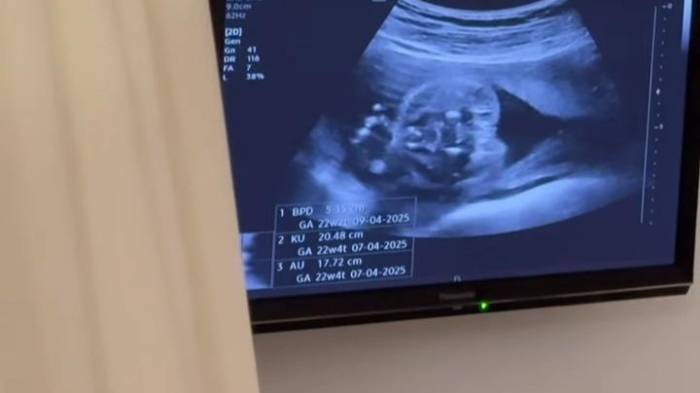

Resulta que en una de las citas de control, nuevamente le realizaron una ecografía a la pareja de Andrade. Ellos, sonreídos viendo a la criatura a través de la pantalla moverse de un lado para el otro, fueron sorprendidos por la doctora, pues no es un niño, sino una niña.

Según los esposos, la especialista estaba el 80% segura de que era niño y por eso se hizo la revelación. “Como todos saben que los planes de Dios son perfectos, estamos esperando una hermosa reina que la vamos a amar con todo nuestro corazón”, expresó Andrés.